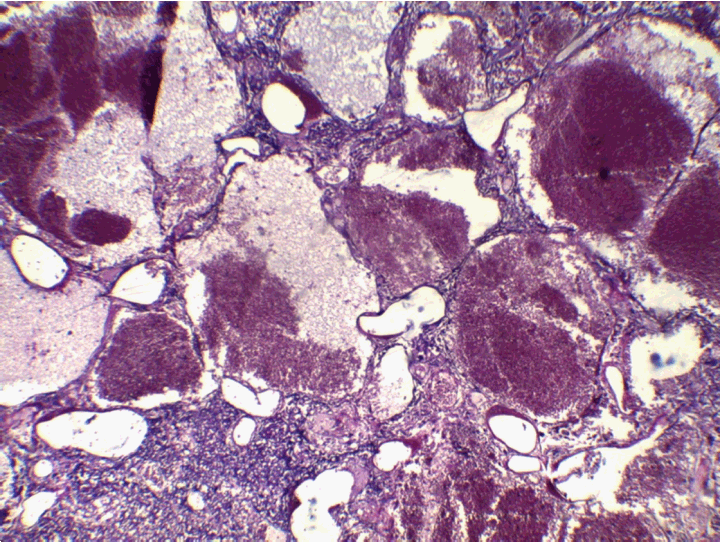

At the pathology laboratory, we received a piece of the left lower limb amputation. (Figure 2) We opened it. Gross examination of the resected distal femur revealed a 22x5 cm intramedullary multicystic hemorrhagic destructive tumor with cortical destruction and extension into the adjacent anterior and posterior soft tissues. The latter component of the mass was larger than the intraosseous tumor. (Figure 3) The articular surface was not involved. We cut the femur in its longest axis with electric saw. (Figure 4) Fixation in 10% neutral buffered formalin for 48 hours and decalcification of bone with nitric acid were performed. Slice of bone section was included in full. Many specimens from soft tissues and the surgical margins were also taken. Microscopic view of histological specimens of tumor stained with hematoxylin andeosin showed prominent blood filled cysts with malignant stroma in septa separating cysts. (Figure 5) (Figure 6) It contained atypical tumor cells oval or round of variable size with osteoblast-like multinucleated giant cells and a variable amount of immature osteoid. (Figure 7) (Figure 8) (Figure 9) (Figure 10) (Figure 11) (Figure 12) Numerous mitotic figures were noted (Figure 13). The tumor was located at 6 cm from the bone limit and 2 cm at the edge of the soft tissues. The resection margins were negative. The marrow, scooped and submitted separately, was negative.

Figure 11: Telangiectatic osteosarcoma with blue spiculated bone.

Figure 12: Telangiectatic osteosarcoma. Malignant osteoid is deposited in a lace-like pattern.

Figure 13: High magnification showing anaplastic cellular features and mitotic activity (arrow).